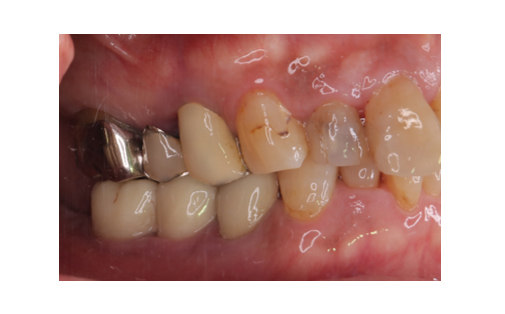

骨造成とインプラント

下顎の骨量が乏しいため骨造成をし、その後インプラント治療を行いました。

かみ合わせも良好でしっかりと機能しています。